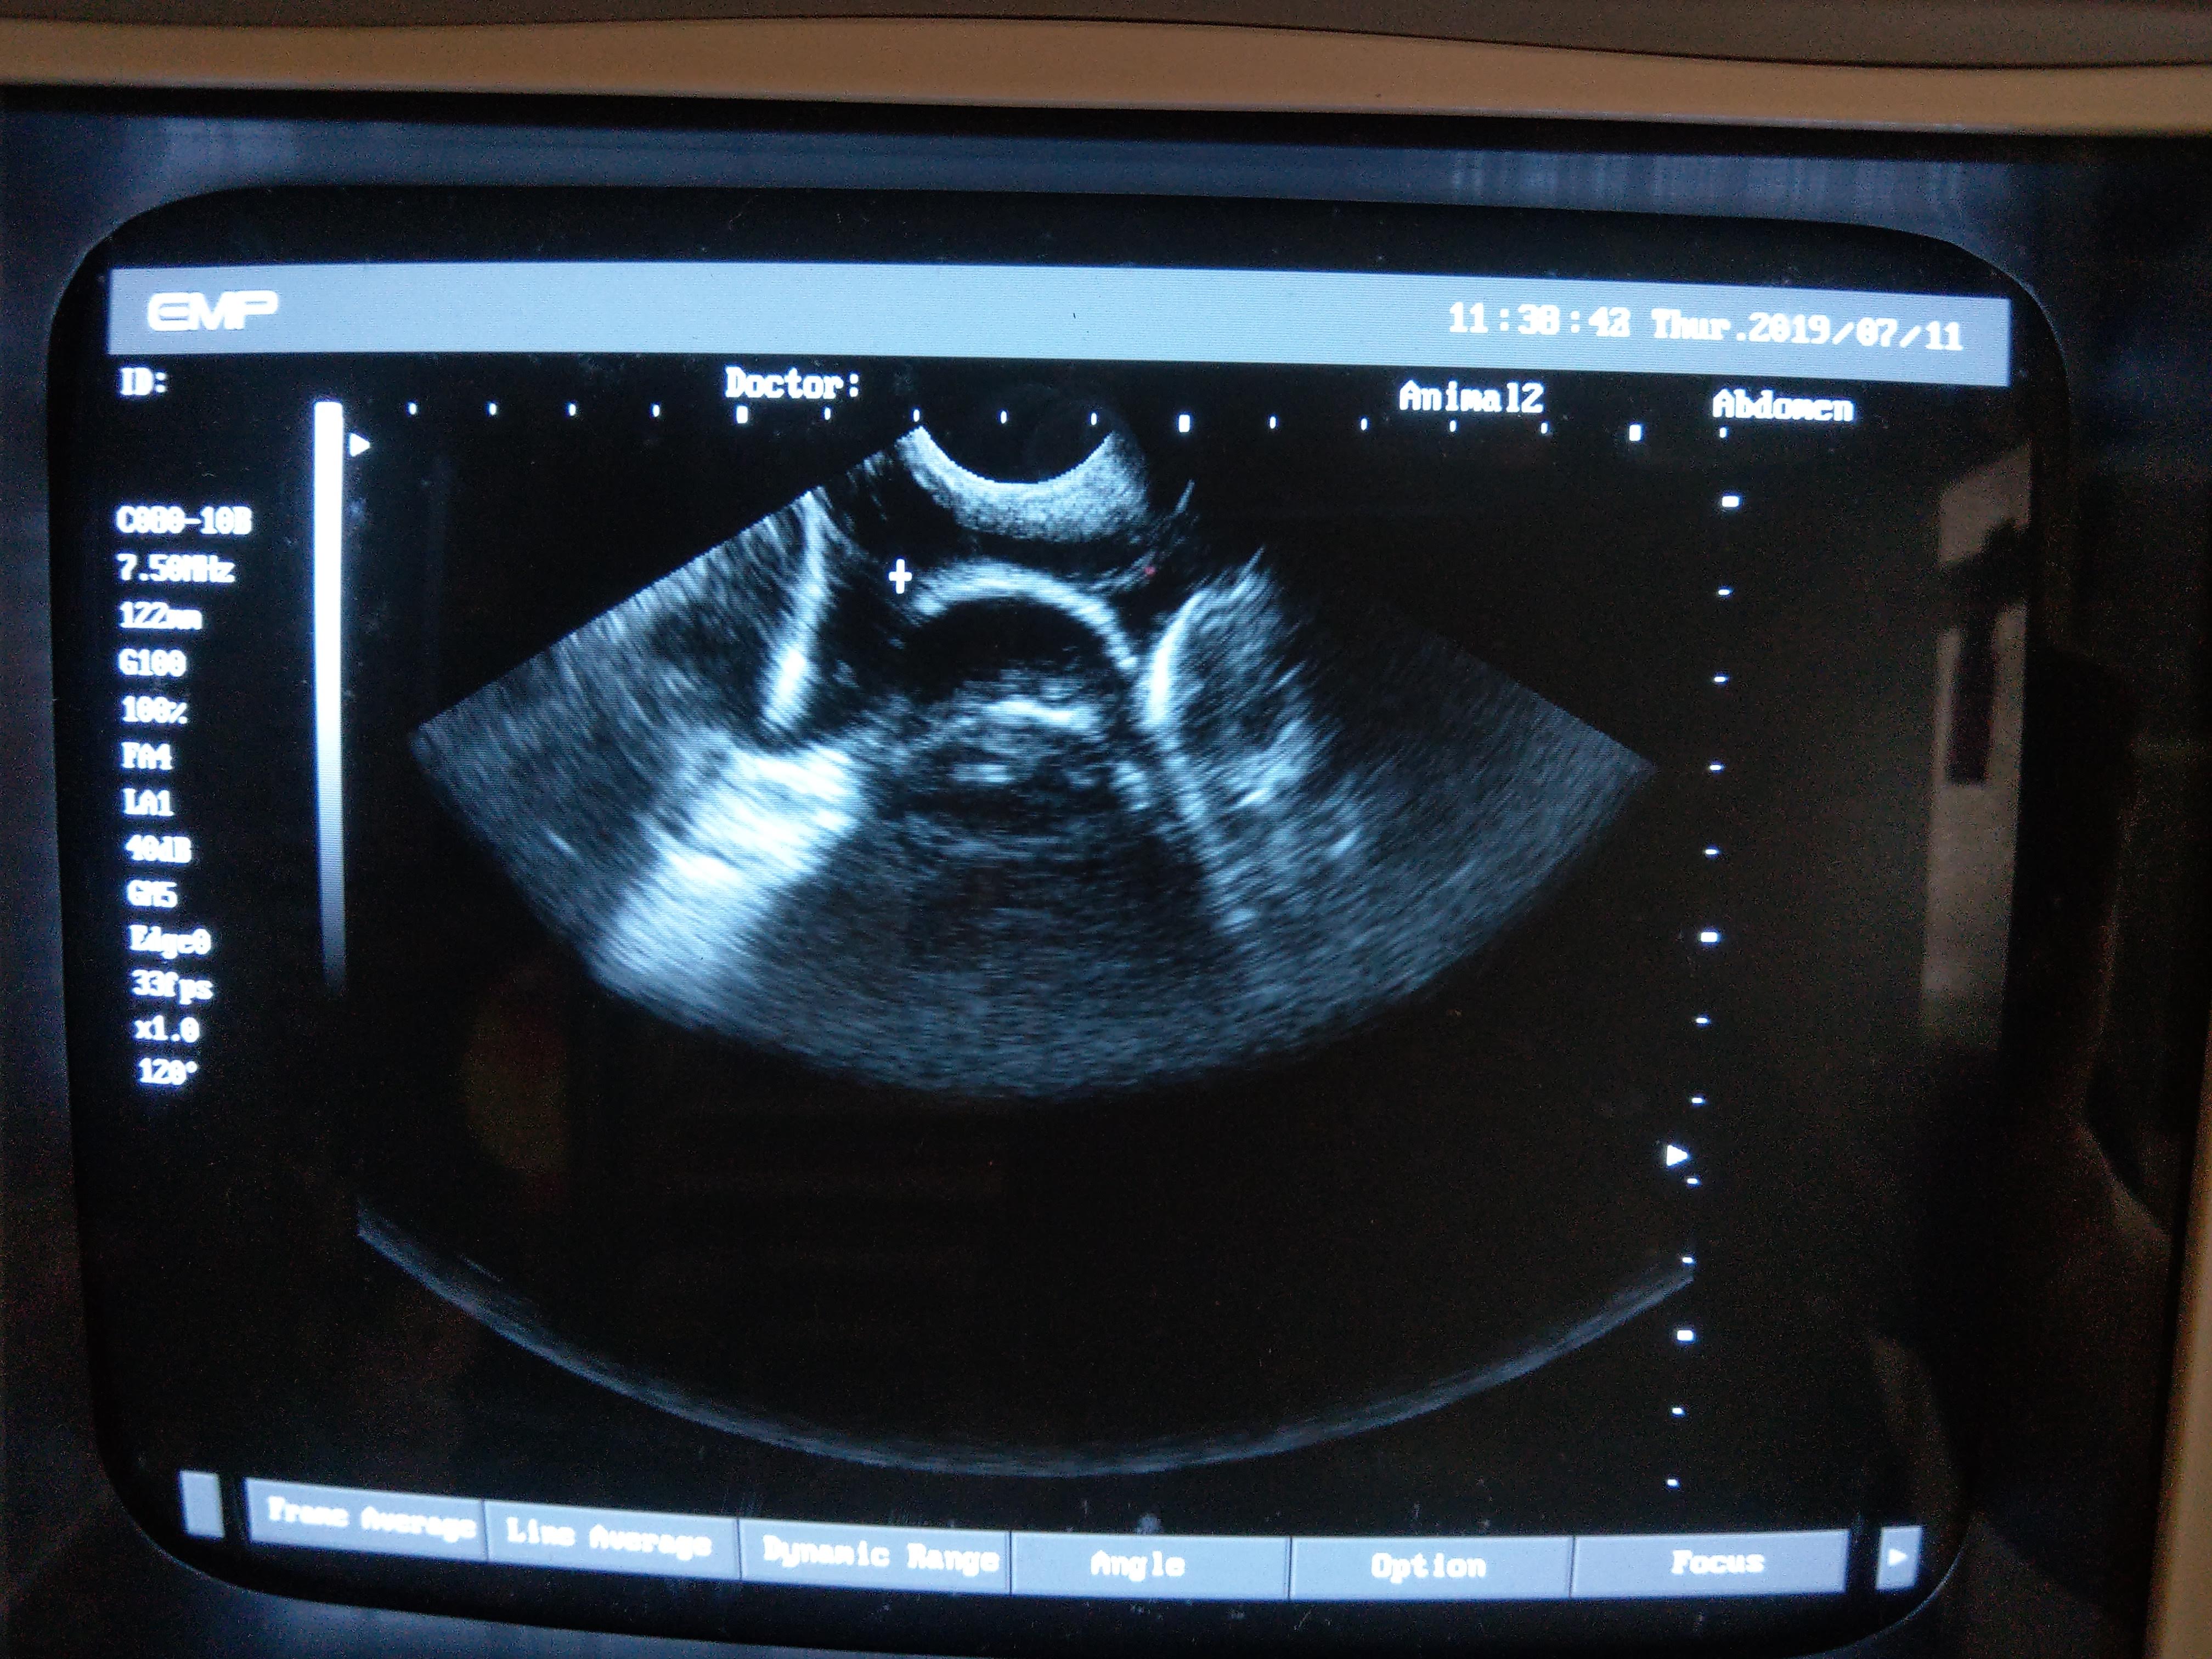

以下是一些記錄照片,有啲圓型冇白邊相信係母龜體內的卵泡,還未完成製蛋過程,還需一段時間才會生蛋。而有白邊的相信是蛋殼的鈣質,體內的蛋已經成熟,隨時準備好產蛋。如果發現有些母龜的蛋在體內己經成熟一段長時間又沒有產下來,就要查證是否有塞蛋等問題。